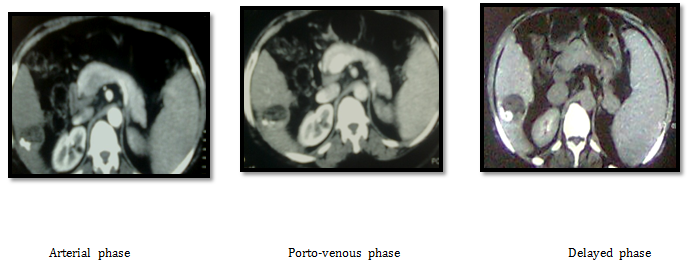

Case number (1), A 55years old female patient known to have hepatitis C virus with right hepatic lobe malignant lesion proved by imaging and elevated AFP. Her CT findings was right hepatic lobe (segment VI) well defined focal lesion of about 5cm showing early enhancement in arterial phase and rapid wash out in porto-venous and delayed phases, mild splenomegaly, no ascites. Her labs before doing any procedure was as follow (AFP 850, ALT 110, AST 90, Direct Bilirubin 1.1, Albumen 3 U/L and Creatinine 0.9). This patient was not candidate for surgery because she is cardiac patient with ejection fraction 38% and she were having poor bleeding profile with INR 1.5, that is medically controlled before starting the procedure.

CT images before doing any procedure: We decided to do RF as a starting treatment. She was complaining of mild post RF syndrome that controlled by medical treatment and after three weeks from RF ablation her AFP drop to 500 (Figure 2)

Figure 2 CT images before doing any procedure.